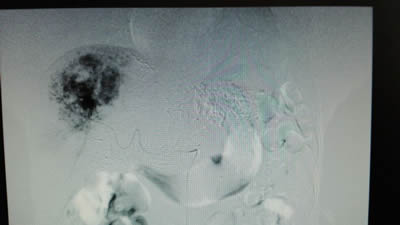

术前:DSA下右肝7×5cm的肝血管瘤成像 术前:DSA下左肝5×4cm的肝血管瘤成像